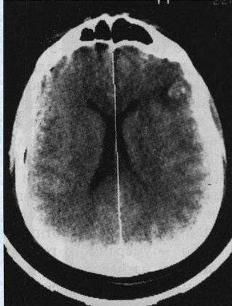

Основним діагностичним стандартом є КТ голови, при якій виявляють вогнищеві зміни в речовині мозку. Часто на КТ знаходять переломи основи та склепіння черепа.

Після того як пацієнт з ЧМТ надходить у приймальне відділення нашої лікарні черговий нейрохірург проводить огляд, і по протоколу діагностики даного захворювання в ургентному порядку призначається комп’ютерна томографія голови і при необхідності шийного відділу хребта.

Після результатів діагностики лікар приймає важливе рішення про тактику лікування даного пацієнта, тобто потрібно точно вияснити чи є покази до оперативного втручання.

Часто під час отримання консервативної терапії стан пацієнта погіршується, в такому випадку роблять контроль КТ голови, і при необхідності пацієнта в ургентному порядку оперують.